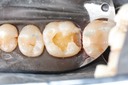

Alan Chinn #2 prep